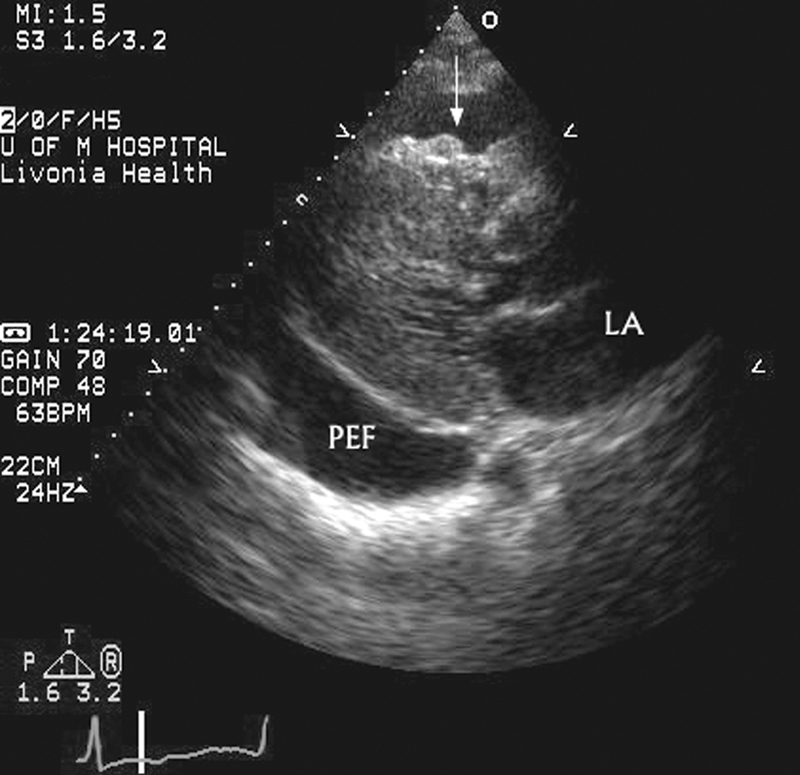

فحوصات تشخيصية لبعض امراض القلب والشرايين التاجية